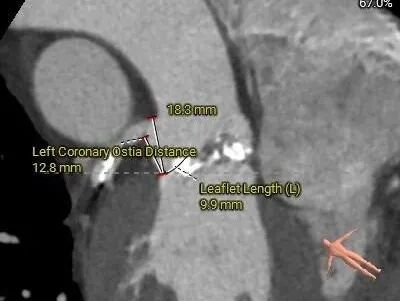

术前CT评估

功能型二叶瓣,瓣叶增厚,R-L间有钙化嵴;大瓦式窦,升主扩张严重横位心

重度钙化,HU 850积分1192mm3

左冠19.4,右冠25.8,综合分析冠脉阻挡风险适中

手术策略讨论

•功能型二叶瓣,瓣叶增厚,R-L间有钙化嵴,重度钙化,钙化于各窦内延伸分布,无冠窦内钙化居多,左、右冠窦下各有部分钙化向LVOT延伸;LVOT接近直筒型,

•左、右冠高度可,切线位测量,左窦瓣叶略长于左冠开口下缘;左主干分叉附近可见钙化分布,